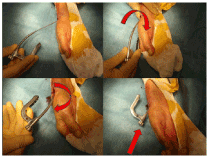

The Nail-o-flex® nail was introduced in 2005. It is a specific nail for fractures of the distal radius. It comprises a distal portion which is perforated and a long, smooth proximal part that is thin and flexible to ensure elasticity. The “Nail-o-flex” ® nail application technique is directly derived from the long bones nailing of the lower limb (Figure 6).

Figure 6. Major point: the nail is introduced in reversed position. It is turned 180° as long as pushed forwards. A “clic” is heard by the time the fracture is reduced

The radius fracture is reduced by manual traction. The nail is inserted at the level of the snuffbox, outside the tendinous areas. The entrance is perforated with a small square point. The nail has an "S" shape. It is inserted with curvature upside down to fit the metaphyseal angle, it is then turned over and entirely inserted. It is stopped by the aiming frame which stumbles on the radial styloid. Locking is performed as for the femur or tibia. The nail is freestanding thanks to its "S" design and its 3 points of support. It is also elastic since the 2/3 of the nail are fine as a pin (2 mm) and automatically realigns the distal epiphysis and keeps the focus open. It must be locked at its. distal part, with at least two epiphyseal screws (Figure 7).